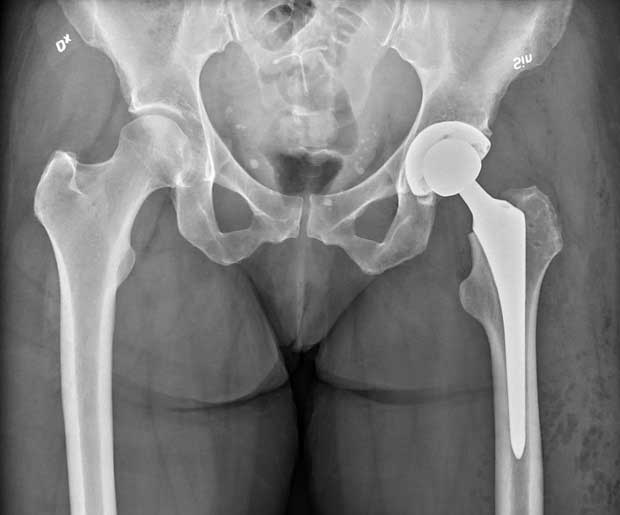

Total Hip Replacement (THR): In a total hip replacement, both the ball (the head of the femur) and the socket (acetabulum) of the hip joint are replaced with prosthetic components. This is the most common type of hip replacement.

Partial Hip Replacement (Hemiarthroplasty): In a partial hip replacement, only the ball portion of the hip joint (the femoral head) is replaced with a prosthetic component. This is typically done when the socket part of the hip joint is still healthy and doesn't need replacement. Hemiarthroplasty is often performed for certain hip fractures.

Revision Hip Replacement: In cases where a previous hip replacement has failed or become damaged, a revision hip replacement may be necessary. This involves removing and replacing the existing prosthetic components with new ones.

Hip Implants Material: The prosthetic components of hip replacements can be made from various materials, including metal, plastic, and ceramic. The choice of material depends on factors like patient age, activity level, and the surgeon's recommendations.